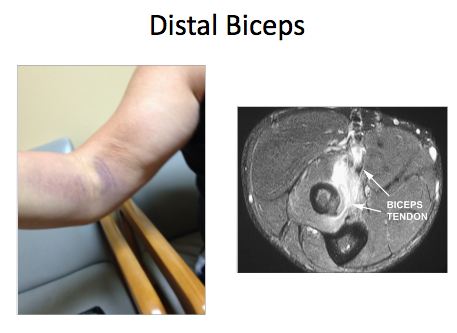

What is this?

Tennis/Golf Elbow

- What parts of the elbow do each present on?

- How should we examine it? 3

- Tennis is on the outside and golf on the inside

- Feel it/reciprocate the pain

- Tennis -resisted wrist extension

- push down on the long finger